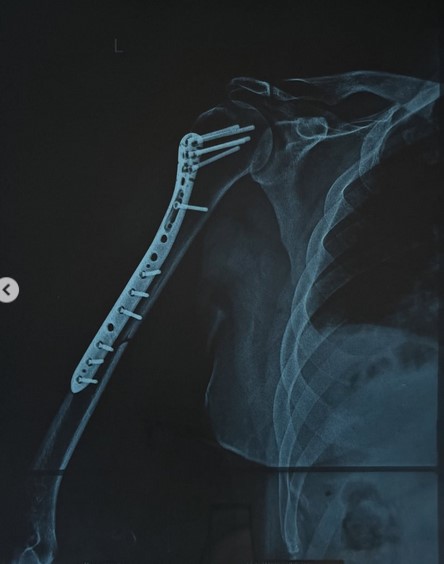

«Όταν θυμάμαι σε ποια κατάσταση μπήκα στην Ευρωκλινική Αθηνών το βράδυ της Πέμπτης, με το χέρι σχεδόν διαλυμένο και σκέφτομαι πόσο γρήγορα θα ανέβω ξανά στη σκηνή την Παρασκευή που έρχεται… μόνο ευγνωμοσύνη μπορώ να νιώσω.

Το “τεράστιο ευχαριστώ” ανήκει στον χειρουργό Γιώργο Μάζη και σε όλο το επιτελείο του, αν και είναι λίγο μπροστά σε αυτό που έκαναν για μένα.

Με χειρούργησαν και μου “έδωσαν” πίσω το χέρι μου και τη δυνατότητα να επιστρέψω εκεί που ανήκω: στη σκηνή!